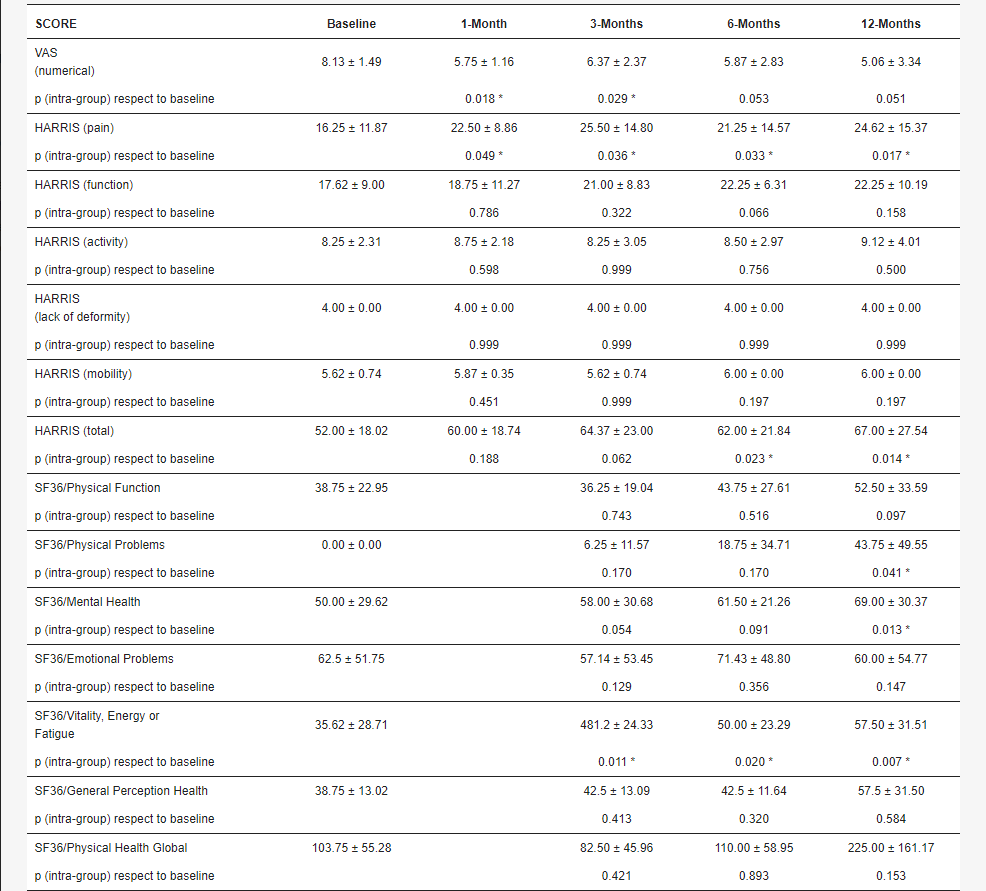

VAS和Harris問卷的結果

關于問卷的結果,在VAS中,我們觀察到開始時疼痛的最小值已經超過一半,最小值為6,最大值為10(7.94±1.50)。在輸注后的整個隨訪過程中,觀察到這種主觀疼痛感有所減輕,在某些情況下達到完全緩解。根據這些數據,手術后疼痛感似乎立即得到改善 (5.75±1.17, p= 0.018),第三個月略有惡化 (6.37±2.37, p=0.029),術后再次下降第六個月 (5.88±2.84, p=0.053) 直到在一年的隨訪中觀察到最低值 (5.29±3.55, p=0.050)。表1中顯示了所有不同的分數和組內值。

對于Harris問卷,在“疼痛”部分,我們觀察到整個研究都有改善,基線 (16.25±11.88) 和最終值 (24.62±15.37) 之間的平均值有超過八分的顯著差異,p=0.017。在基線時,我們發現平均值為16.25±11.87,而在隨訪結束時,該值上升至24.62±15.37,p=0.017。

關于“功能”部分,我們觀察到接受治療的患者的一般功能能力有所改善,盡管p值在統計學上不顯著。觀察到大約五個點的客觀可測量恢復,初始值為17.62±9.00,在隨訪結束時達到22.25±10.19,p=0.097。

在“活動”中,觀察到在12個月的隨訪期間,這些活動保持增加的趨勢,從開始時的平均值8.25± 2.31到結束時的9.12±4.02。

最后,就Harris問卷的總體而言,盡管一名患者在一年內獲得了最低值之一,但與基線相比平均值有顯著改善,從平均值52.00±18.02到67.00±27.55。關于SF-36問卷,身體狀況的基線值遠低于人口平均值,精神狀態的基線值略好,但也低于平均值。在整個隨訪過程中,總體身心健康值持續增加。